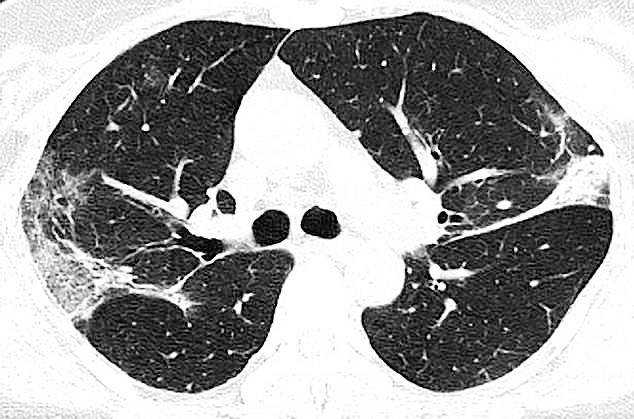

सार्स की वजह से नवंबर 2002 से जुलाई 2003 तक करीब 8000 लोग बीमार हुए थे. इनमें 774 लोगों की मौत हो गई थी. इन सभी के फेफड़ों का एक्स-रे और सीटी स्कैन एक जैसा था. सभी के एक्स-रे और स्कैन में फेफड़े के बीच सफेद चकत्ते मिले थे. कोरोना वायरस की वजह से सभी की छाती में म्यूकस बन रहा था.

छाती में म्यूकस बनने की वजह से सांस लेने में दिक्कत आती है. साथ ही छींक आती है. क्योंकि आपको सांस लेते समय पर्याप्त हवा नहीं मिलती. इस एक्स-रे को देखकर ऐसा लगता है कि इन मरीजों के फेफड़ों में हवा की जगह सफेद मौत भरी हुई है. (फोटोः पीटीआई)